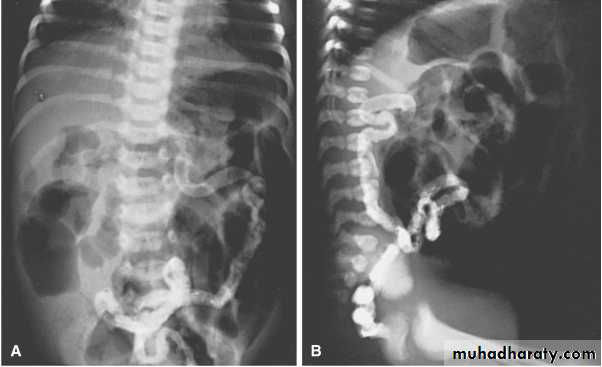

Meconium ileus